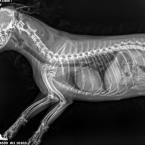

Nasmu 4 rocneme maltezakovy diagnostikovali na zaklade rtg stdca zvacsene srdiecko...u fenky sme si vsimli unavu a ze casto posedava a prestala sa hrat. Chceme sa spytat ci na diagnozu a podavanie luekov staci len rtg srdca, a do akej miery je zvacsene. Ziadne ine priznaky sme si nevsimli.Veterinár radí - bezplatné poradenstvo pre vášho psíka

Nasmu 4 rocneme maltezakovy diagnostikovali na zaklade rtg stdca zvacsene srdiecko...u fenky sme si vsimli unavu a ze casto posedava a prestala sa hrat. Chceme sa spytat ci na diagnozu a podavanie luekov staci len rtg srdca, a do akej miery je zvacsene. Ziadne ine priznaky sme si nevsimli.Odpovede veterinárov